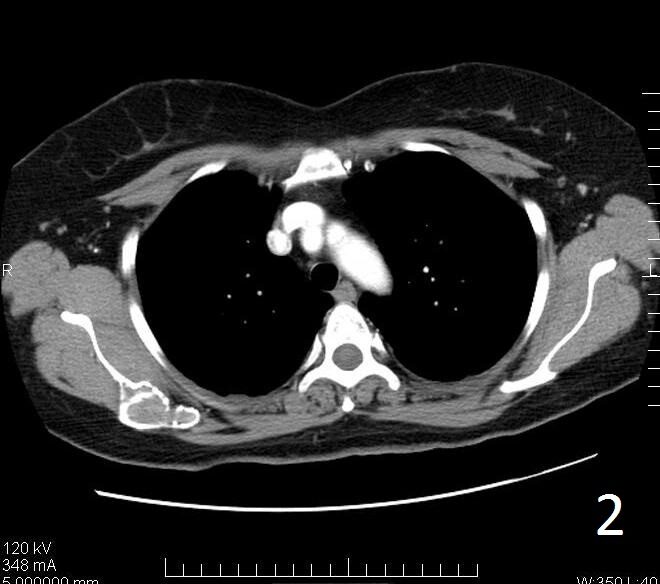

• Useful to determine the extent of the lesion as well as ground glass appearance (Fig. 2-3)

• Well defined borders

• Possible endosteal scalloping lesion

• Areas of mineralization within.

Fig. 2. Axial CT reconstruction of the shoulder illustrates a lytic lesion of the right scapula consistent with fibrous dysplasia. There is a ground glass appearance.